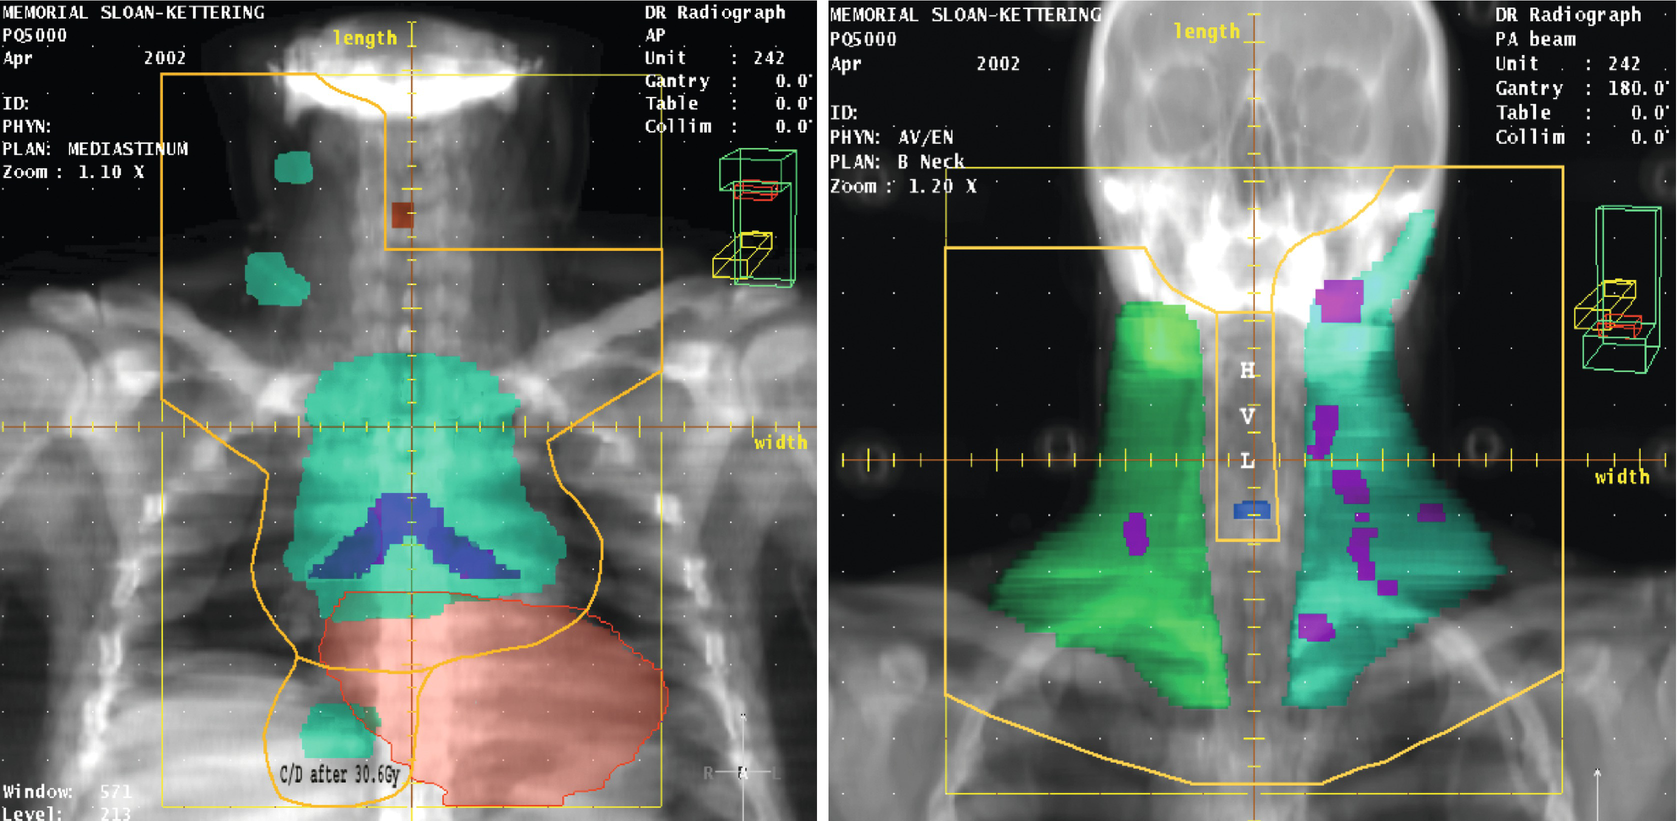

Hodgkin's lymphoma treatment plan

Pet Guided Omission Of Radiotherapy In Early Stage Unfavourable Hodgkin Lymphoma Ghsg Hd17 A Multicentre Open Label Randomised Phase 3 Trial The Lancet Oncology